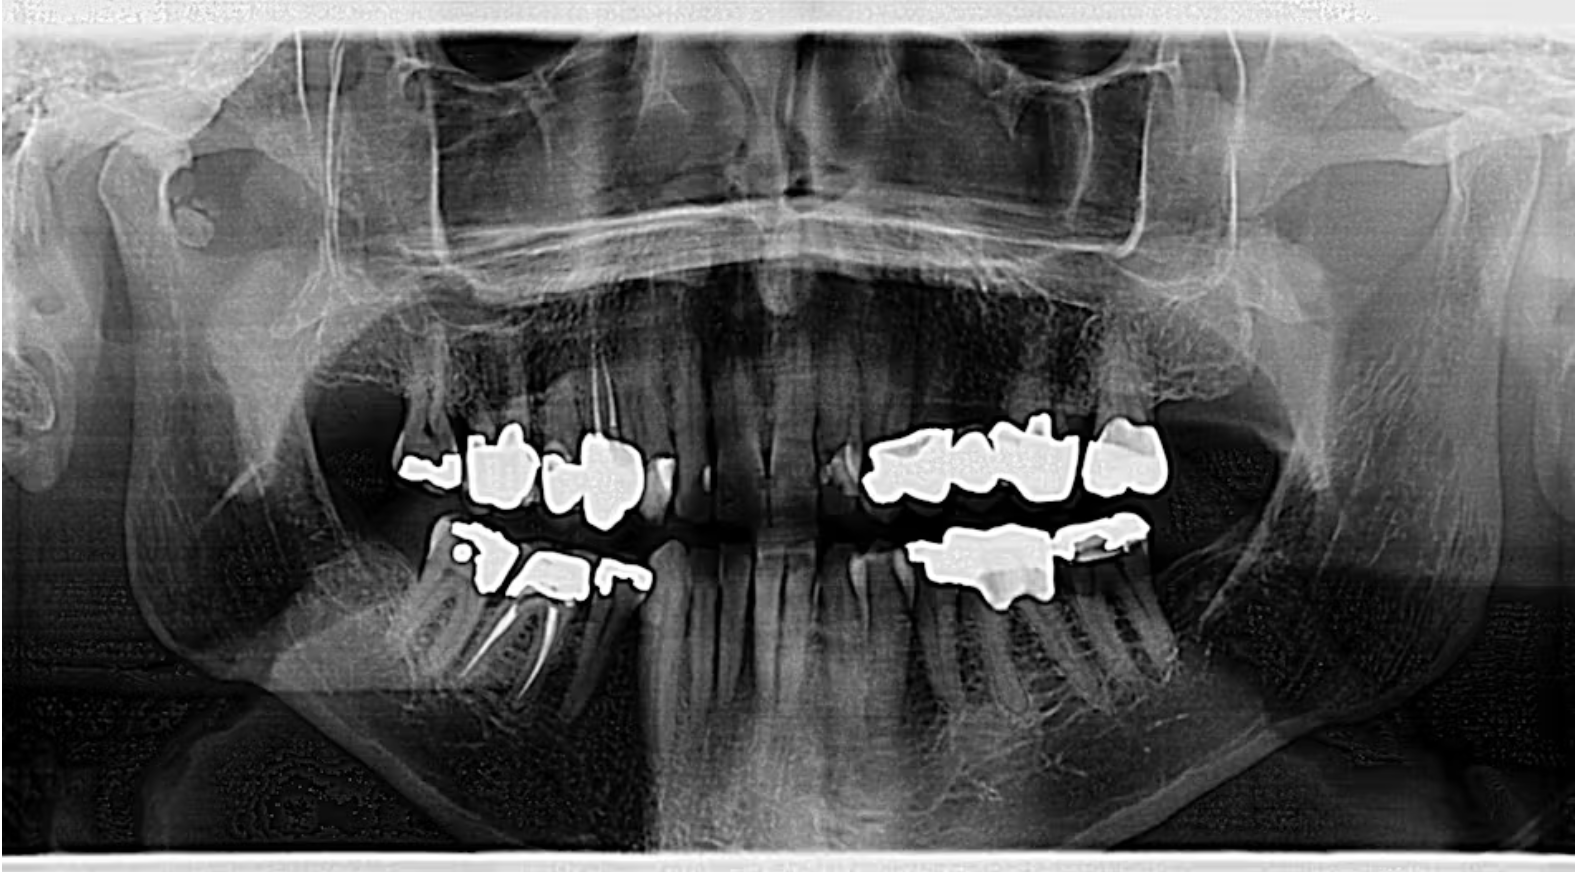

Một bệnh nhân nam 78 tuổi được chuyển đến bác sĩ phẫu thuật hàm mặt để đánh giá một vùng cản quang được phát hiện tình cờ trên phim X-quang toàn cảnh (hình 1). Bệnh nhân là người khỏe mạnh, năng động; tiền sử y khoa chỉ đáng chú ý với tăng huyết áp đã được kiểm soát tốt và trào ngược dạ dày – thực quản mức độ nhẹ. Thuốc đang sử dụng gồm lisinopril và omeprazole, không có tiền sử dị ứng thuốc.

Vùng bất thường trên phim toàn cảnh xuất hiện dưới dạng nhiều cấu trúc cản quang, ranh giới rõ, nằm phía dưới lồi cầu và phía trước cổ lồi cầu phải.

Khám lâm sàng cho thấy bộ răng người trưởng thành khỏe mạnh với khớp cắn hạng I ổn định. Hàm dưới có biên độ vận động bình thường: há tối đa 44 mm, đưa ra trước 8 mm, vận động sang phải và trái mỗi bên 8 mm, không lệch đường giữa khi há miệng. Có thể sờ thấy tiếng lạo xạo nhẹ tại TMJ phải, nhưng không có đau khi ấn vào khớp hoặc cơ vùng mặt.

Chẩn đoán phân biệt tại thời điểm này bao gồm:

- Thoái hóa khớp với các gai xương lành tính

- Bệnh lý chondromatosis hoạt dịch

- Bệnh lắng đọng calcium pyrophosphate (CPPD)